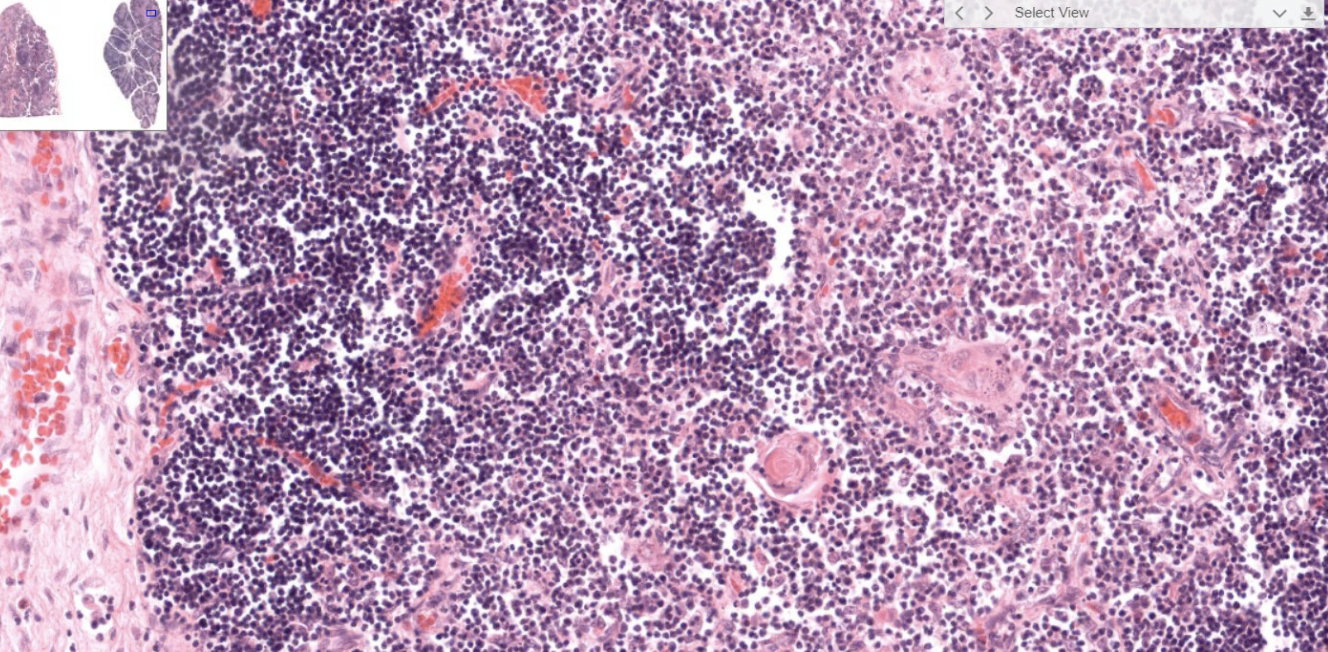

Lymphatic System

Lymph node

High endothelial venule (HEV)

Structure

Lymphatic nodules

Secondary nodule

形成抗體

GC: Germinal center (產生抗體, B cell)

MnZ: Mantle zone(T cell)

粉紅色: Reticular cell